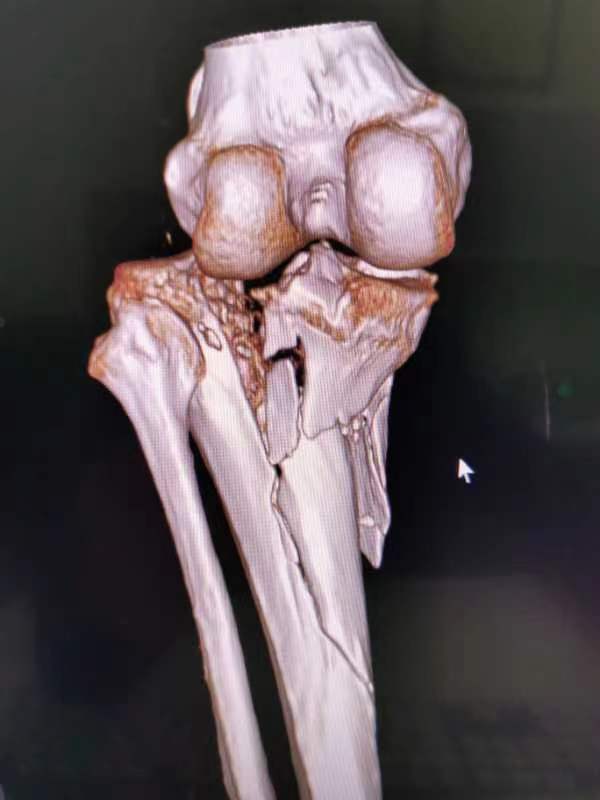

胫骨平台粉碎性骨折术前术后